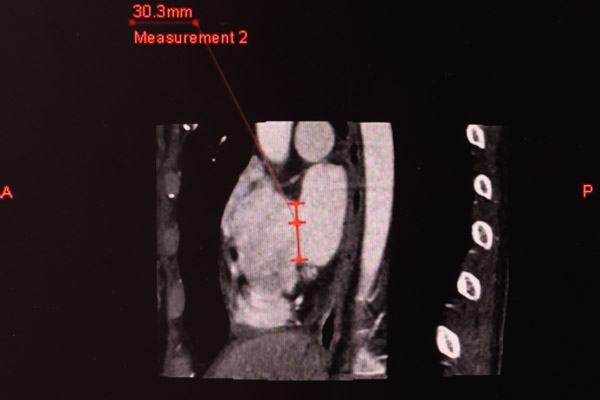

“下腔型房间隔缺损不是介入治疗的适应症,这种先心病过去均需要通过开放手术才能解决。”我院心血管内科副主任医师陈世忠介绍,但是现在这一情况有所改变,下腔型房缺本身还有几种亚型,通过我院配备有目前最先进的320排CT,除了能够重现人体脏器的立体结构外,还能实时反映患者整个器官功能状态和血流运行的情况,可以清晰地看到房间隔缺损的位置以及大小,明确房室关系及血管走向,遴选出合适封堵的亚型,辅助我们制定最优手术方案。

在与杨某充分沟通后,患者强烈要求进行微创手术治疗,希望医生能够想想办法,由于患者心脏缺损边缘至下腔静脉的距离不足1mm,对于介入手术来说难度极大,为了解决其面临的难题,心血管内科召集放射科和超声科团队一起讨论会诊, 通过320排CT生成的动态立体图像,精确计算,反复对比研究,再三斟酌决定大胆尝试,用了足足两天时间做好了手术方案和术前准备。